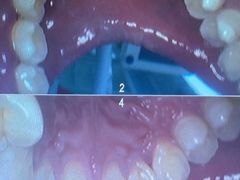

• 牙博士口腔品牌连锁(杨浦店)

• -牙博士口腔品牌连锁(杨浦店)

橙子麻麻 | 21-10-26